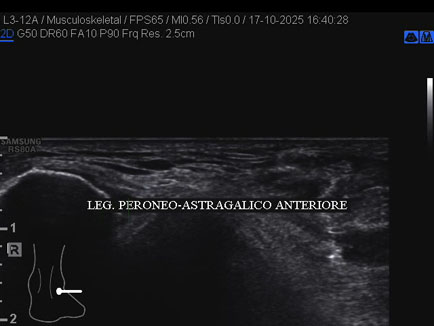

Ecografia del: 17/10/2025

Età Paziente: M

Commento all'esame: rottura del fascio antero-superiore del legamento fibulo-talare anteriore con integrità del fascio postero-inferiore in giovane calciatore.

Conclusioni: rottura del fascio antero-superiore del legamento fibulo-talare anteriore destro (tear of the anterosuperior bundle of the right anterior talofibular ligament).